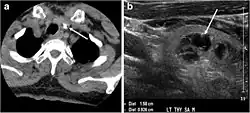

- Fig. 4. A 45-year-old male patient presented with anterior mediastinal metastatic PTC lesions and occult primary on imaging. Histopathology examination of the resected thyroid gland revealed micro-foci of PTC; the largest, in the isthmus, measured 4 mm. a transverse greyscale ultrasound of the thyroid demonstrates homogeneous gland with normal echogenicity and size. No focal lesion or micro-calcifications. b Non-enhanced CT scan obtained as part of PET/CT examination shows a heterogeneous, large, relatively dense anterior mediastinal mass (white arrow) with peripheral calcification (arrowheads). Thyroid gland has normal CT appearance with no abnormal FDG uptake (not shown).[1]